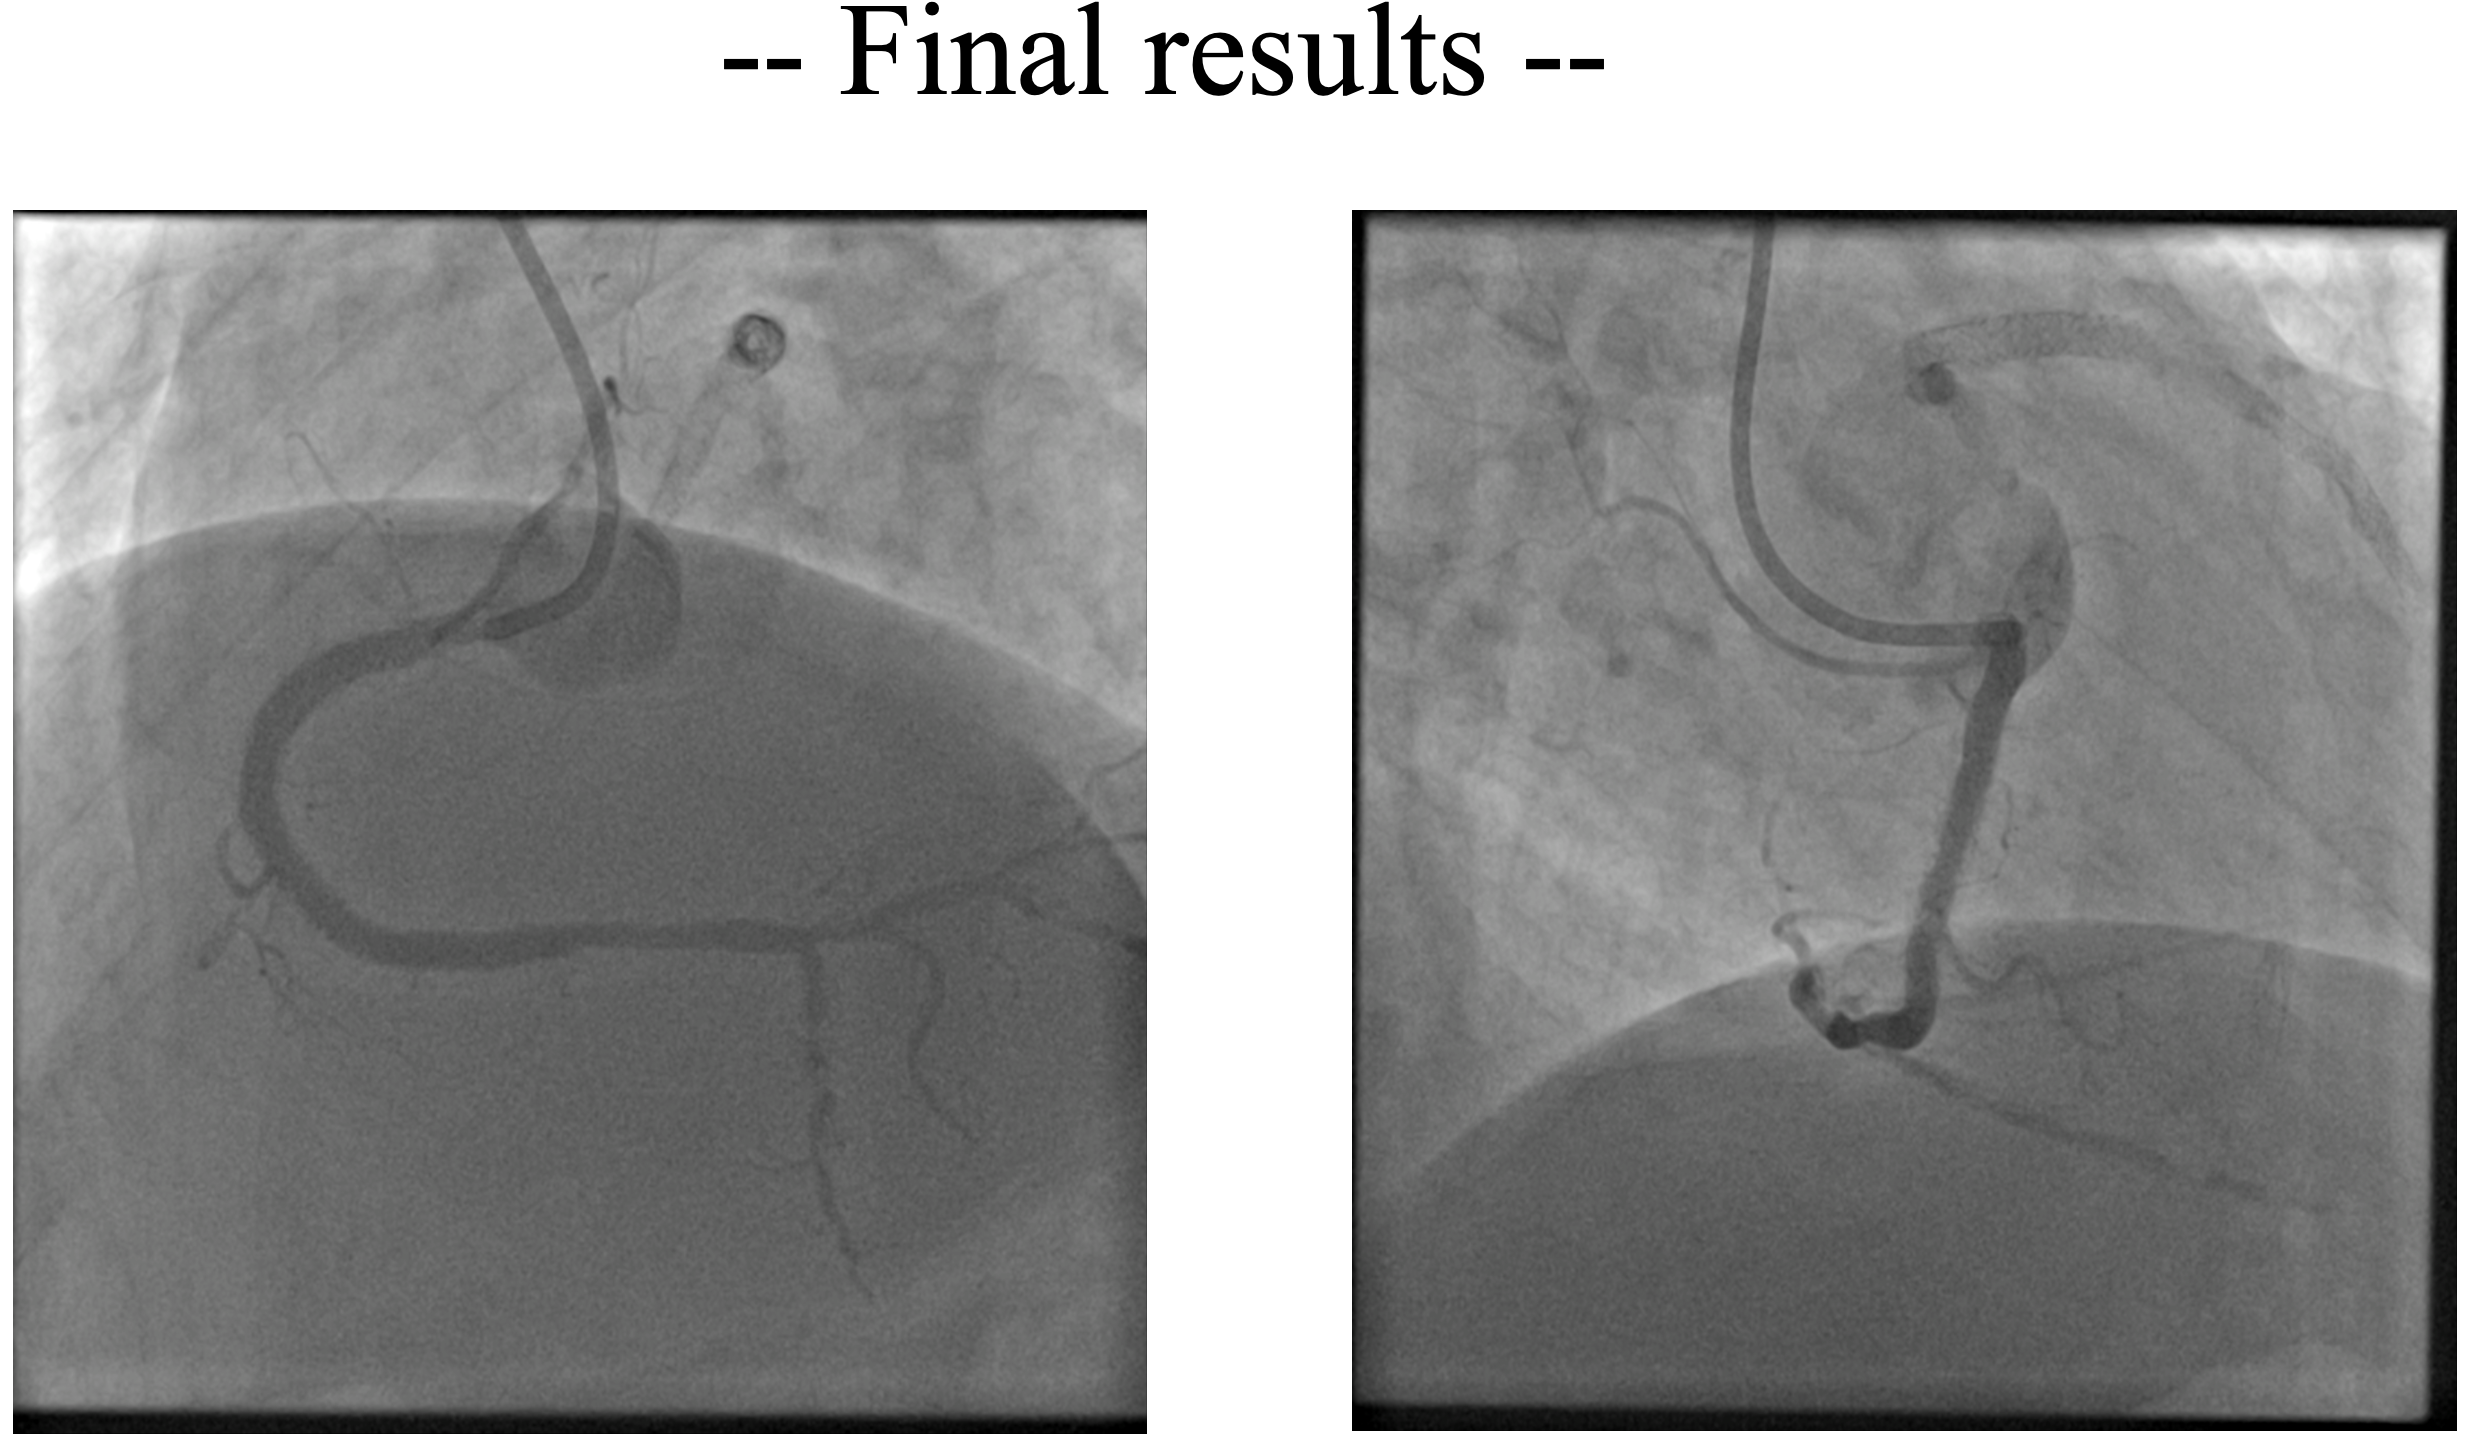

Right radial access was obtained, right coronary ostium was selectively cannulated with 6F Hockey stick guiding catheter. Runthrough NS wire was advanced into the distal RCA. Optical coherence tomography (OCT) using saline was performed to minimize the risk of worsening kidney function. OCT revealed concentric calcification with both eruptive and non-eruptive calcific nodules protruding through multiple stent struts, resulting in stent underexpansion (MSA 3.67 mm2). Red thrombus was also present around the lesion. Predilatation with a 3.5 x15 mm cutting balloon using controlled, prolonged inflation up to 12 atm was attempted; a persistent ¡°waist¡± was observed, indicating inadequate lesion modification. For better lesion preparation, then we performed Intravascular Lithotripsy (IVL) using Shockwave 3.5 x12 mm C2 IVL balloon and 80 pulses were delivered at mid RCA. IVL balloon expansion was satisfactory at 6 atm, and no residual waist observed. OCT after IVL showed calcium fractures at multiple sites and compression of protruding calcifications, with increased luminal area. Further dilation was performed with 3.5 x 15 mm NC balloon. This was followed by delivery of a 4.0 x 20 mm paclitaxel-eluting balloon (DEB) at the mid RCA for 60 seconds. Final angiography and OCT evaluation showed excellent results, with MSA improved from 3.67 mm©÷ to 7.71 mm©÷.

Case Summary